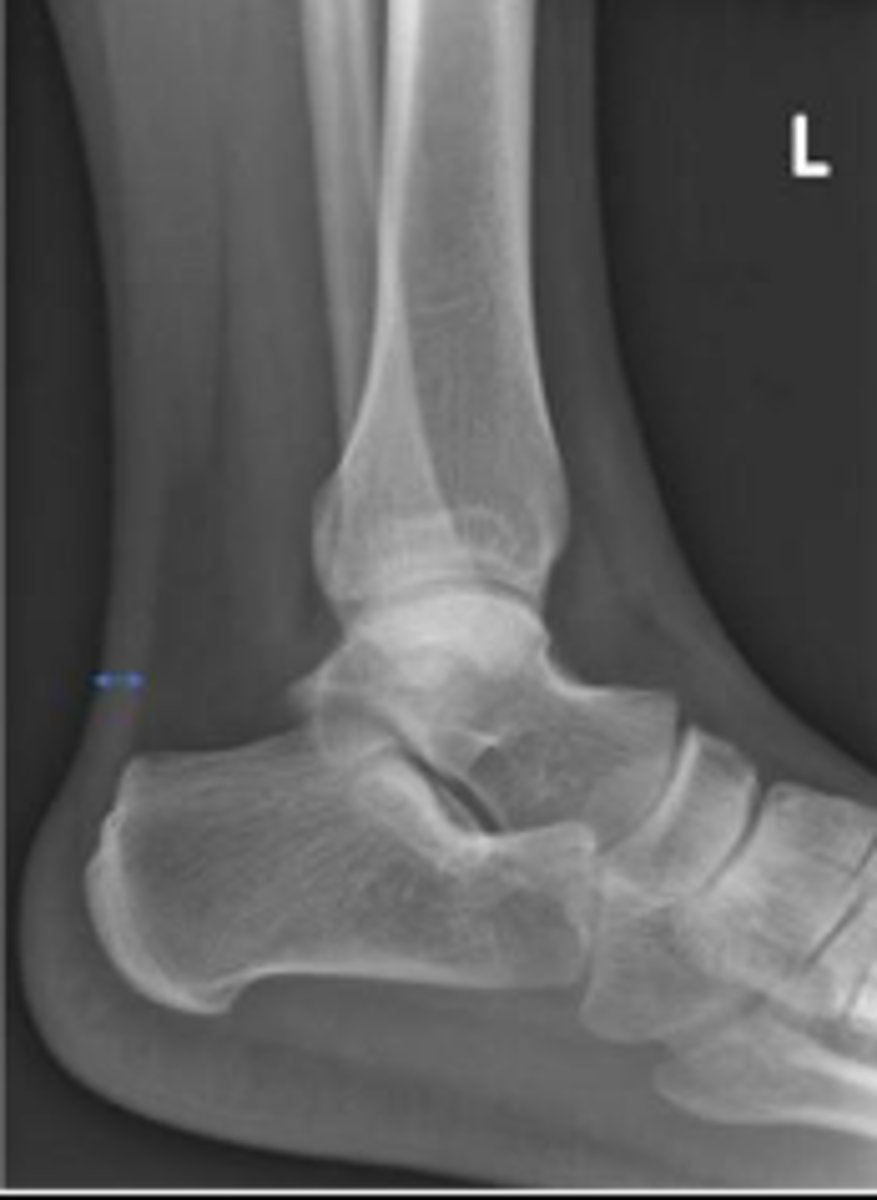

Left AP ankle

What is the name of the radiographic view?

Left internal oblique ankle